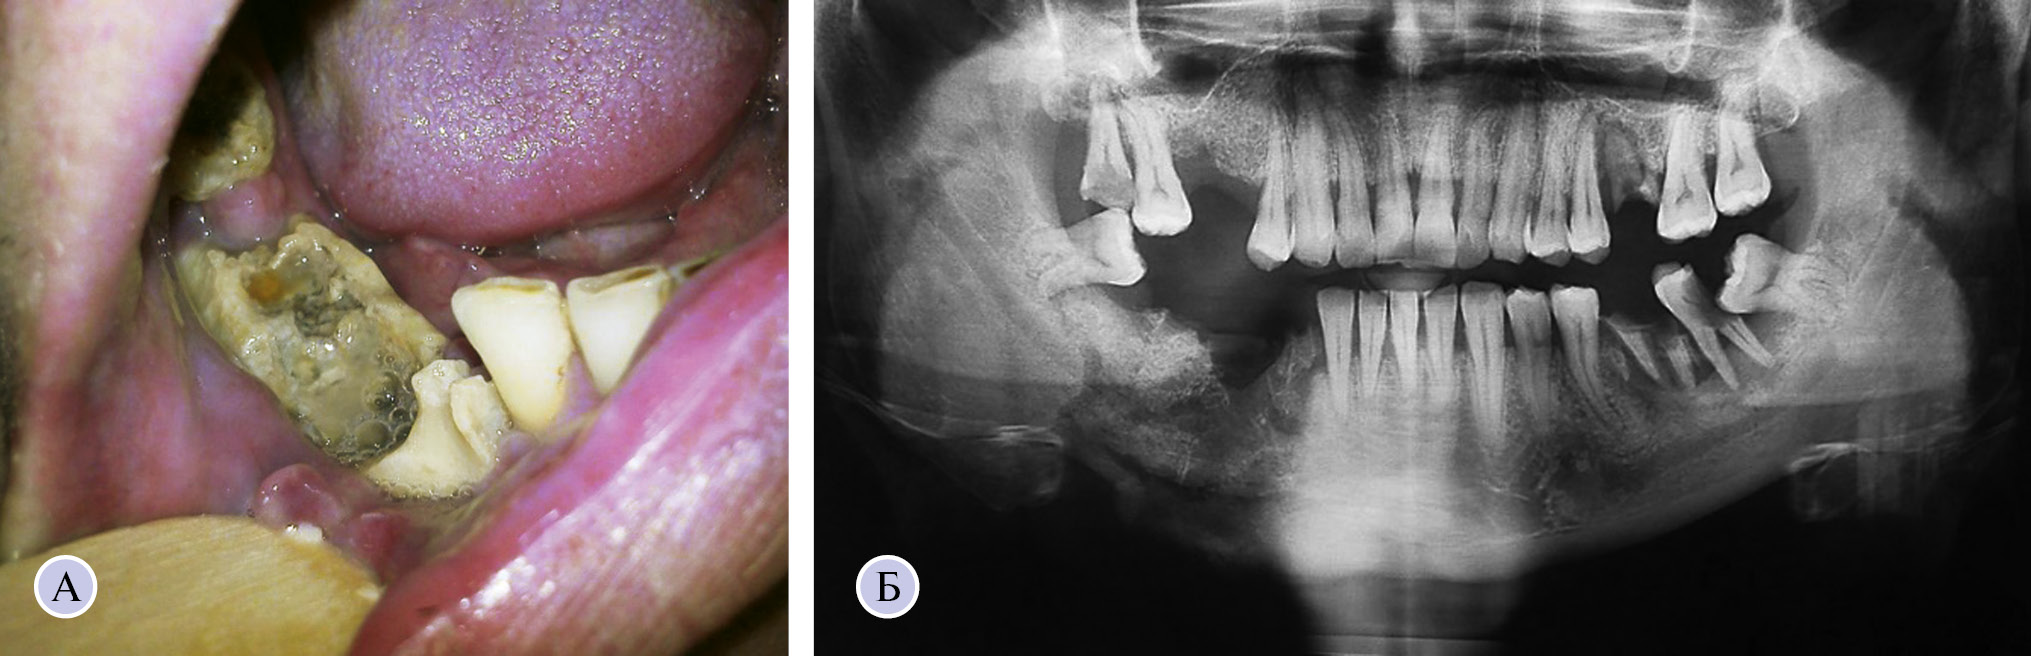

Клинико-рентгенологическая картина токсического остеонекроза характеризуется своей специфичностью (рис. 1).

Рис. 1. Изменения в полости рта (А) и на ортопантомограмме (Б) при токсическом остеонекрозе нижней челюсти

Характерно тяжелое и атипичное течение патологического процесса, захватывающего более одной зоны челюсти, быстрое распространение воспаления на здоровые участки кости, гипоэргический тип общей реакции с вялым клиническим течением, несоответствие видимых границ некроза челюсти реально существующим, постоянные ноющие боли, выраженная гнойная экссудация из свищей, хроническая интоксикация, рецидивы заболевания даже после радикальных оперативных вмешательств [3]. Основным клиническим проявлением токсического остеонекроза является расшатывание и выпадение зубов с обнажением костной ткани, что служит входными воротами для инфекции. Микроорганизмы, обитающие в полости рта, заселяют данные участки, тем самым усугубляя патологический процесс в пораженной кости. Полость рта отличается богатым составом микрофлоры. Доминирующее место обитающих в ротовой полости микроорганизмов как по видовому разнообразию, так и по количеству занимают бактерии [4]. Выделяют резидентные и транзиторные виды. Резидентная микрофлора включает в себя относительно постоянные виды бактерий, характерные для определенного биотопа, и способна к быстрому восстановлению в случае ее нарушения. Транзиторная флора состоит из непатогенных или условно-патогенных микроорганизмов, которые заселяют полость рта в течение ограниченного периода времени, не вызывая заболевания. Однако в случае нарушений или гибели резидентной микрофлоры представители транзиторной замещают освободившуюся нишу и вызывают развитие патологии [5]. При этом хронический некротический процесс в челюстных костях переходит в фазу обострения с возникновением выраженной гнойной экссудации, формированием абсцессов и флегмон мягких тканей лица и полости рта, что сопровождается выраженной интоксикацией организма и приводит к возникновению угрозы генерализации гнойно-воспалительного процесса.